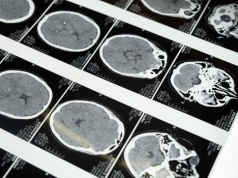

Robotyczna angiografia mózgu może skracać czas zabiegu i zachować pełne bezpieczeństwo – pokazuje nowe badanie. Artykuł Robot przyspiesza angiografię – badanie pokazuje krótszy czas zabiegu i 100% skuteczności pochodzi z serwisu Alert Medyczny.